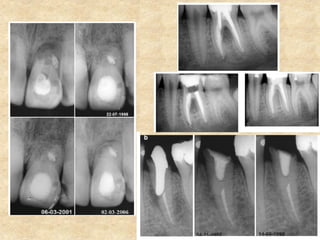

1. Pulp Capping:

• MTA has been proposed as a potential medicament for capping of pulps

with reversible pulpitis because of its excellent tissue compatibility. It is

much superior to the routinely used calcium hydroxide based on the tissue

reaction and the amount and type of dentin bridge formed.

• Calcium hydroxide is associated with tissue necrosis and inflammation

during the initial period of placement but no such inflammation or

necrosis was seen in the pulp tissue adjacent to MTA.

• With MTA, dentin bridge after pulp capping was seen at about 1 week

which steadily increased in length and thickness within 3 months of

capping whereas following pulp capping with calcium hydroxide, the

dentin bridge was less consistent and had numerous tunnel defects.

• Since there is no pulpal necrosis, pulp tissue heals faster with MTA.

Aeinehchi et al in 2003 reported a 0.28 mm thick dentin bridge by 2

months which increased to 0.43 mm by 6 months. The dentin bridge

formed with calcium hydroxide was only 0.15 mm by 6 months.

1. Pulp Capping: •MTA has been proposed as a potential medicament for capping of pulps with reversible pulpitis because of its excellent tissue compatibility. It is much superior to the routinely used calcium hydroxide based on the tissue reaction and the amount and type of dentin bridge formed. • Calcium hydroxide is associated with tissue necrosis and inflammation during the initial period of placement but no such inflammation or necrosis was seen in the pulp tissue adjacent to MTA. • With MTA, dentin bridge after pulp capping was seen at about 1 week which steadily increased in length and thickness within 3 months of capping whereas following pulp capping with calcium hydroxide, the dentin bridge was less consistent and had numerous tunnel defects. • Since there is no pulpal necrosis, pulp tissue heals faster with MTA. Aeinehchi et al in 2003 reported a 0.28 mm thick dentin bridge by 2 months which increased to 0.43 mm by 6 months. The dentin bridge formed with calcium hydroxide was only 0.15 mm by 6 months.